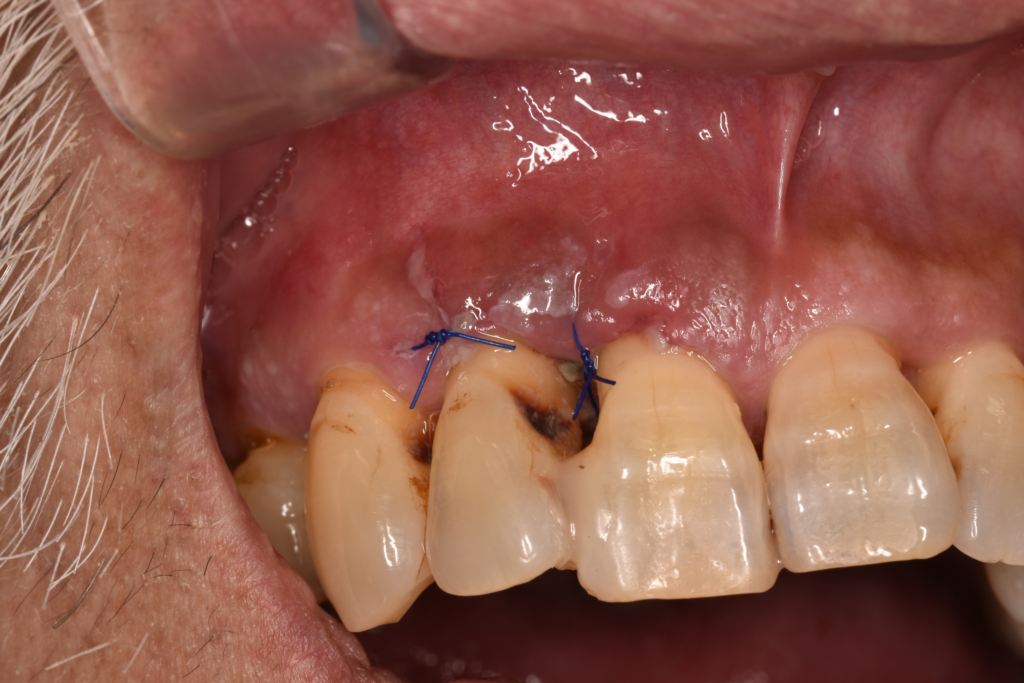

↑歯周外科治療をおこなった後はどうしても歯肉が下がってしまいます。

複数の部位で歯周外科治療をおこないましたが、まだタイミングを探っている場所もあります。SRPの反応を見ながら、介入のタイミングを見ています。